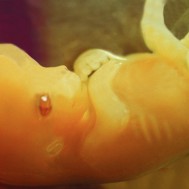

Baby: Week 7

At week 7 all essential body parts are present and accounted for!

All essential body parts are present and accounted for. Your ankles have formed, your arms are long and bend at the elbows. With basic physiology in place, rapid growth and weight gain are the next steps![1]

You are intricately detailed, but still so tiny, only about 3/4 inch (20 millimeters) long.[2]